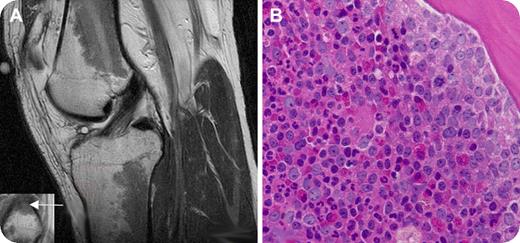

A 27-year-old man presented with a complaint of several months of progressive left knee pain with ambulation. An MRI scan of the left knee revealed extensive intermediate-low-signal intensity within the bone marrow in the diametaphyseal regions of the distal femur and proximal tibia (panel A, sagittal T2-weighted image of knee joint) and the epiphysis of the proximal fibula (panel A inset, coronal T1-weighted detail of fibular epiphysis; the arrow shows the bone marrow abnormality). The patient denied a history of knee trauma and was otherwise healthy. He had no knee abnormality on examination. There was no enlargement of lymph nodes, liver, or spleen.

The abnormalities on the MRI scan, when viewed in the absence of known hematologic abnormalities, were initially attributed to red marrow reconversion, which may be secondary to athletic activity. However, similar findings can indeed be seen in myeloproliferative disorders and marrow replacement disorders. Clinicians should be aware of unusual presentations of hematologic disorders in seemingly healthy patients with abnormal bone marrow signal on MRI scans.